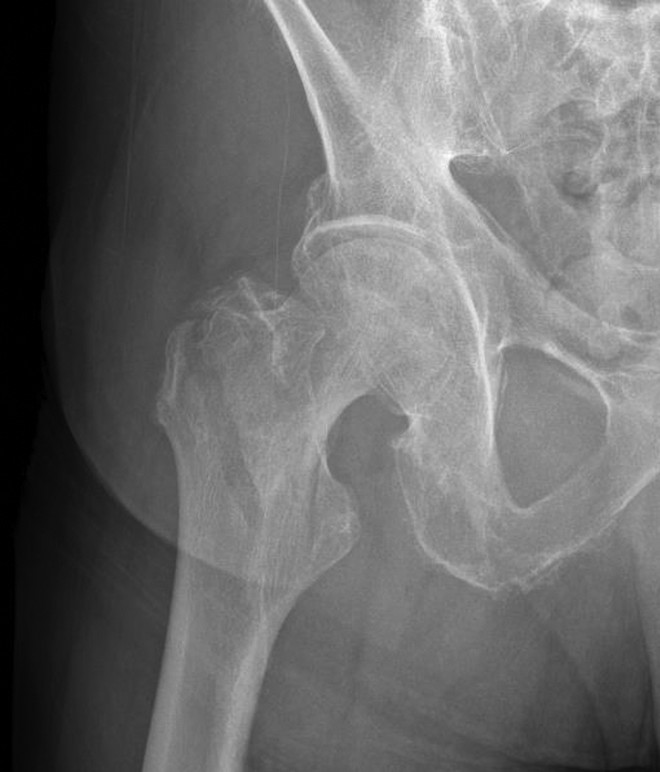

植入物的选择主要取决于骨折的稳定性和外侧皮质的完整性。稳定型股骨粗隆间骨折通常具有完整或复位良好的后内侧皮质支撑(图6),这样可以帮助股骨近端分布应力并承受内侧压力。与此不同,不稳定型骨折在使用髓外固定时往往难以保持股骨近端的复位。这类骨折通常包括:因粉碎或大块骨折块损伤的内侧股骨距,延伸至转子下区域的骨折,反斜形骨折,或是涉及外侧皮质的经转子骨折。(图7-10)

图10. 不稳定型经粗隆骨折(AO/OTA分型 31-A3型骨折)。